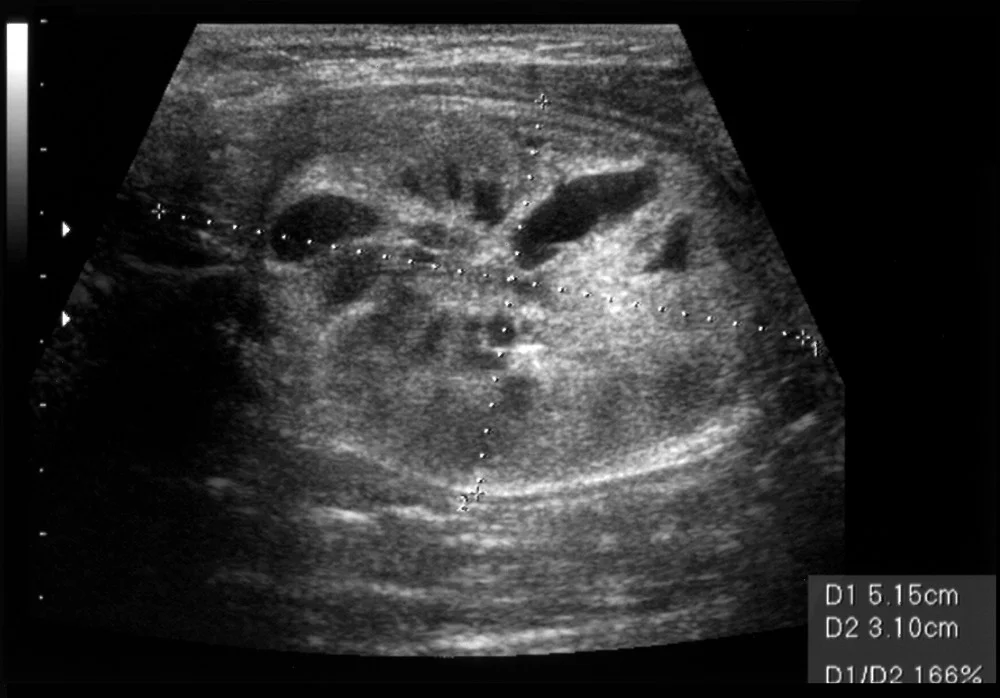

초음파 검사에서 보이는 악성 의심 소견

전문의가 주의 깊게 보는 포인트 5가지

1. 미세석회화

• 결절 안에 하얀 점들

• 갑상선유두암의 특징적 소견

2. 경계 불분명

• 주변 조직과 경계가 흐릿

• 침습적 성장 의미

3. 세로로 긴 모양

• 가로보다 세로가 긴 타원형

• Taller-than-wide 소견

4. 혈류 증가

• 결절 내부 혈관이 많음

• 도플러 검사에서 확인

5. 주변 조직 침범

• 갑상선 피막을 뚫고 나감

• 진행된 암의 소견

실제 영상의학과 전문의 설명 "이 5가지 소견 중 2개 이상 해당되면 세침흡인검사를 권장합니다. 초음파만으로는 100% 확진할 수 없기 때문에 조직검사가 꼭 필요합니다." (영상의학과 전문의)

3. 갑상선 초음파

검사 내용

1. 결절 크기, 개수, 위치

2. 결절 내부 성상 (고형, 낭성, 혼합형)

3. 경계, 모양, 석회화

4. 혈류 분포

5. 림프절 상태

K-TIRADS 분류 (한국 갑상선 영상 보고 및 데이터 시스템)

1. 1점: 정상

2. 2점: 양성

3. 3점: 낮은 의심

4. 4점: 중등도 의심

5. 5점: 높은 의심

비용: 5~10만 원

소요 시간: 10~15분

대한갑상선학회 진료 지침